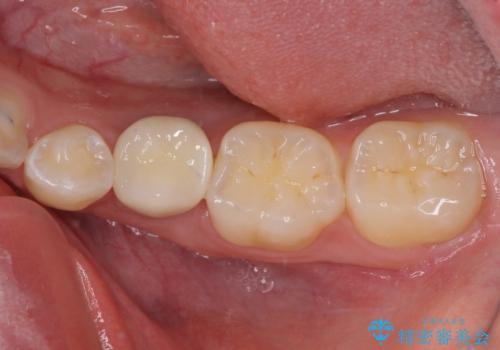

矯正治療が終わるタイミングに合わせてインプラントの埋入を行っていたので、矯正治療を終了すると同時にセラミック補綴治療を行えました。

短期間でしっかりと治療を終えることができました。